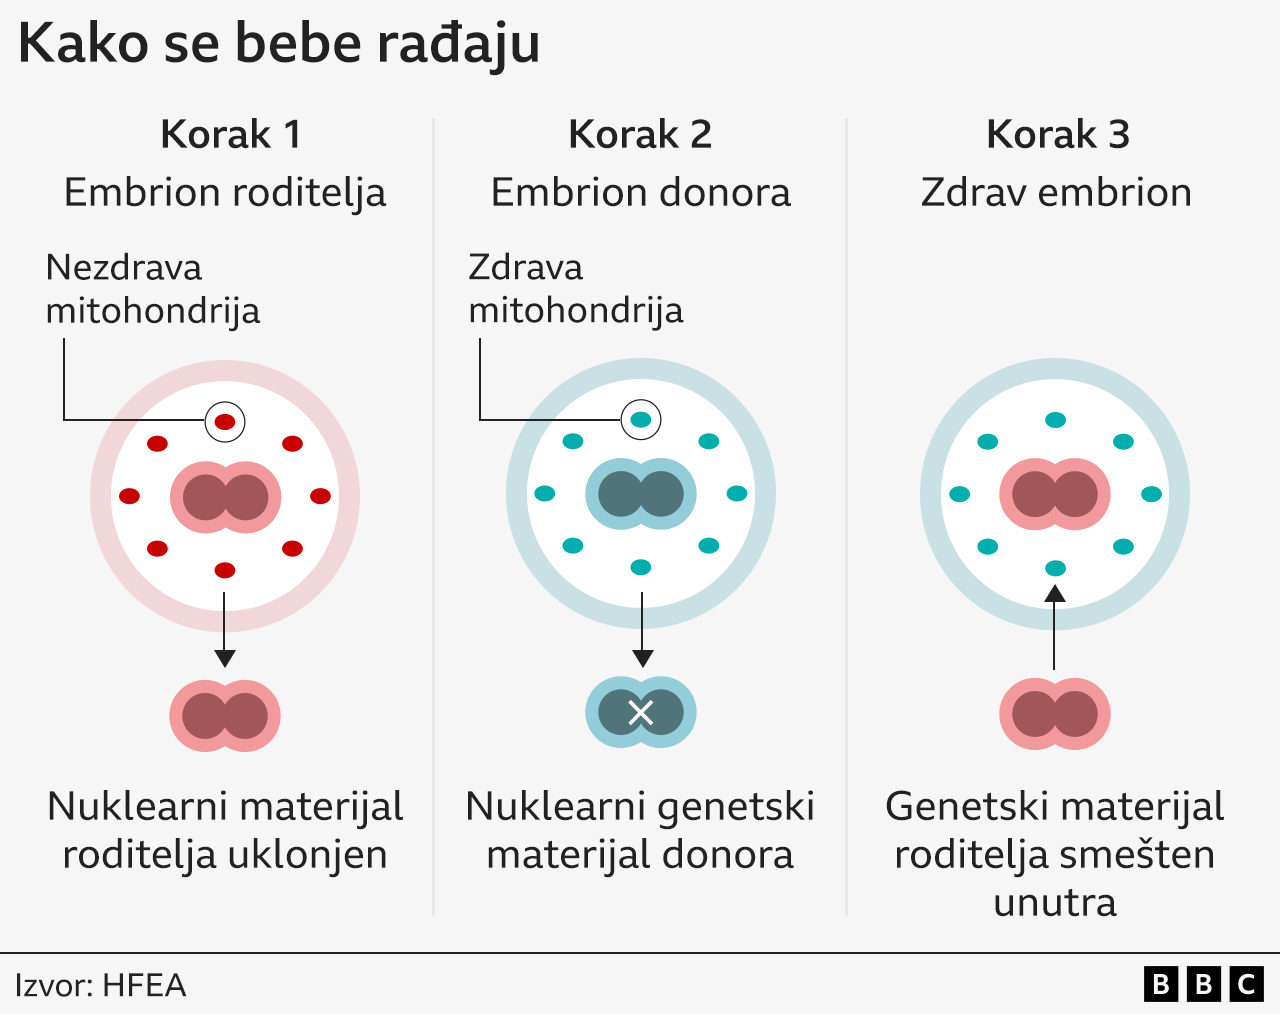

Metoda, čiji razvoj su predvodili britanski naučnici, kombinuje jajnu ćeliju i spermu majke i oca sa drugom jajnom ćelijom žene koja donira zdrave mitohondrije.

Zato ova pionirska metoda oplodnje koristi genetski materijal oba roditelja i žene koja donira njene zdrave mitohondrije.

Oplodnja jajne ćelije i majke i donorke vrši se očevom spermom u laboratoriji.

Embrioni se razvijaju dok DNK iz spermatozoida i jajne ćelije ne formira par struktura koji se zovu pronukleusi.

Oni sadrže genetski plan za izgradnju ljudskog tela, kao što su boja kose i visina.

Pronukleusi se uklanjaju iz oba embriona, a DNK roditelja se ubacuje u embrion sa zdravim mitohondrijama.

Dete koje se začne ovim postupkom genetski je povezano sa njegovim roditeljima, ali ne bi trebalo da ima mitohondrijsku bolest.